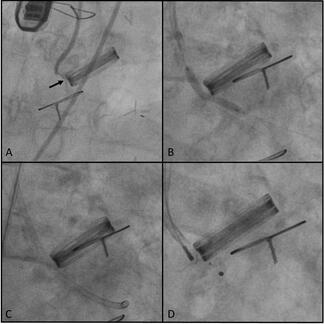

Dimitrios Karelas, MD; Konstantinos Giannopoulos, MD; Ioannis Tsiafoutis, MD; Savvas Nikolidakis, MD

An 89-year-old man with a dual-chamber pacemaker implanted 4 years ago presented with pocket erosion and pacemaker exterorization through the left anterior chest wall. He had a known diagnosis of bullous pemphigoid, histologically confirmed 2...